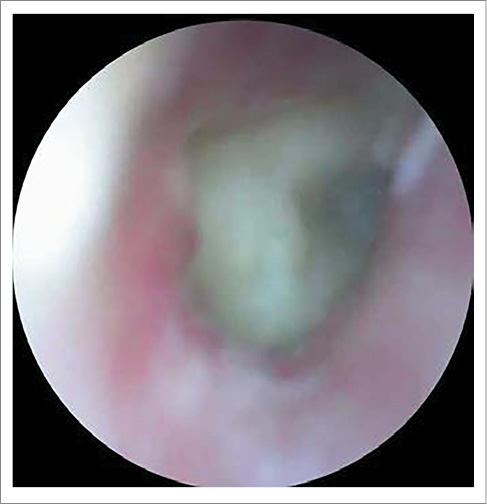

AS – околоушная, заушная область не изменена, при пальпации безболезненна. При отоскопии: наружный слуховой проход широкий, свободный, БП утолщена, местами гиперемирована, в передних отделах визуализируется центральная перфорация диаметром 2 мм, при выполнении пробы Вальсальвы из перфорации поступает скудное гнойное отделяемое (рис. 2).

Рис. 2. Отоскопическая картина слева при поступлении: БП утолщена, местами гиперемирована, в передних отделах визуализируется центральная перфорация диаметром 2 мм.